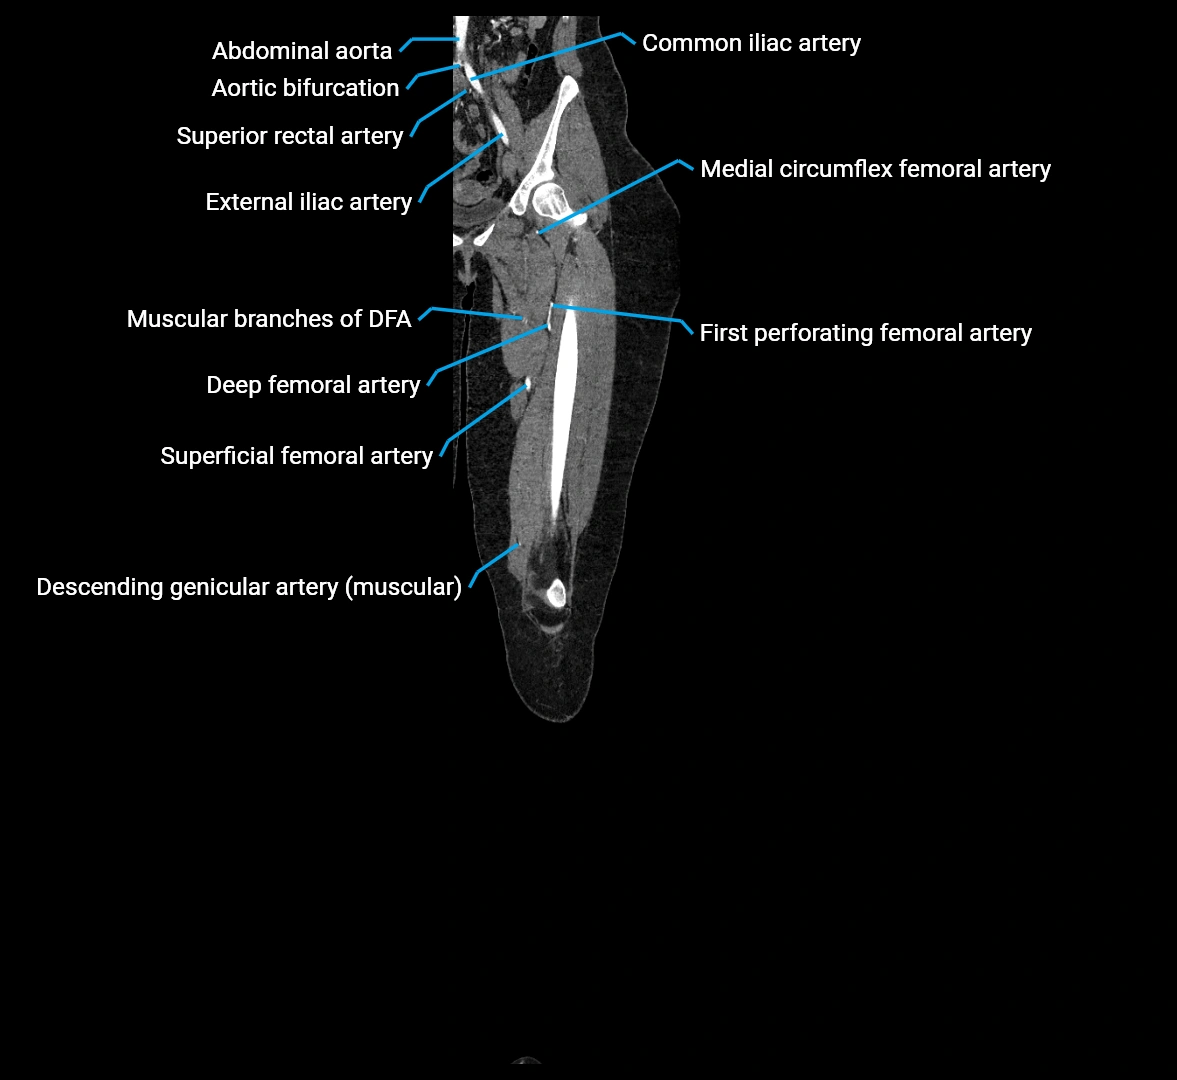

The abdominal aorta is the continuation of the thoracic aorta, beginning at the level of the aortic hiatus of the diaphragm (T12 vertebra) and terminating at the level of the L4 vertebra where it bifurcates into the right and left common iliac arteries. It lies slightly to the left of the midline and courses anterior to the vertebral bodies, surrounded by the retroperitoneal structures of the abdomen.

The abdominal aorta gives off numerous visceral and parietal branches, supplying the abdominal organs, pelvic structures, and lower limbs. It is the main conduit of oxygenated blood from the heart to the abdomen and lower body. The aorta is clinically significant as the common site of aneurysm, dissection, atherosclerosis, and traumatic injury.

Branches

• Unpaired visceral branches: celiac trunk, superior mesenteric artery (SMA), inferior mesenteric artery (IMA)

• Paired visceral branches: middle suprarenal arteries, renal arteries, gonadal arteries (testicular or ovarian)

• Parietal branches: inferior phrenic arteries, lumbar arteries, median sacral artery

• Terminal branches: right and left common iliac arteries

Contrast-enhanced CT (CTA):

• Gold standard for abdominal aortic imaging

• Provides excellent detail of lumen, wall, aneurysm, thrombus, and branch vessels

• Multiplanar and 3D reconstructions help in aneurysm measurement, stent graft planning, and dissection evaluation